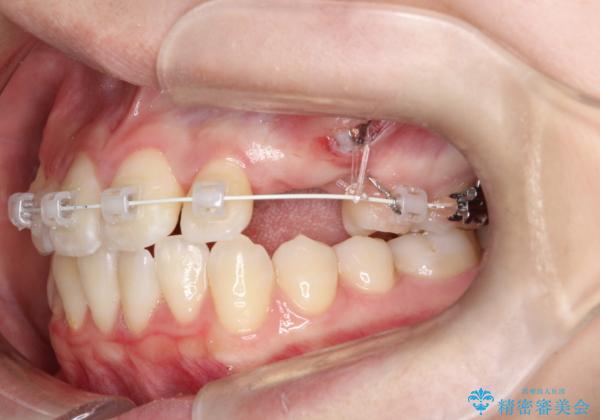

【埋伏歯】犬歯の牽引を行った矯正歯科治療

左側犬歯が埋伏していましたが、第一小臼歯(4番目の歯)を抜歯したことでできたスペースに牽引し、右側の飛び出した八重歯を含め、歯全体を整列することができ患者様も満足していただきました。

犬歯牽引を行うかはCTを撮影し判断を行なっています。